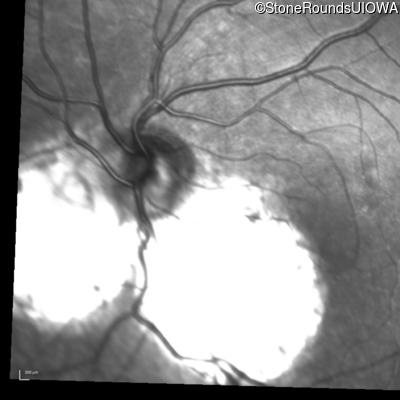

Infrared Fundus Photograph - Right - 20/40 +2

Exemplar